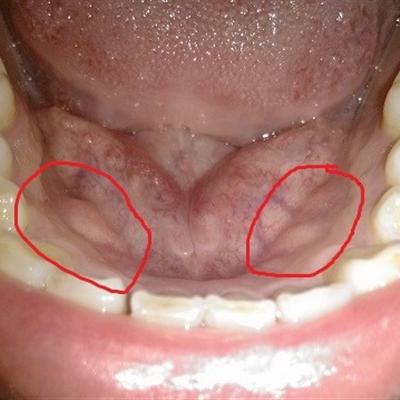

Pharyngitis patients all know that the early symptoms of chronic pharyngitis are mainly foreign body sensation in the throat, which can not go up or down, and often accompanied by nausea and vomiting, especially when brushing teeth in the morning, accompanied by dry cough and expectoration. So we must do a good job of the disease related work, so how long can follicular pharyngitis be good?.

First, if not actively treated, it will develop more symptoms, such as dry mouth, bitter mouth, dry throat, itchy throat, cough, sore throat, white sputum, sometimes accompanied by more or less strong sticky secretions, often making a sound of "singing".